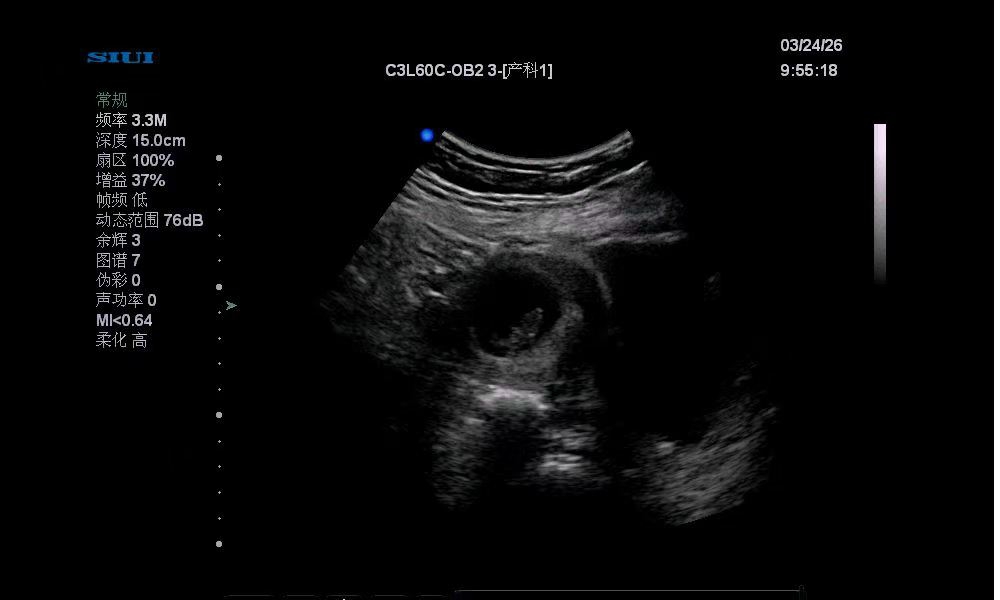

按末次月经算,我这都66天了,今天查出来胎心胎芽

今天去查正常,医生说宝宝很健康

还说b超看没有60几天,也就40几天的样子

所以算到现在也就45天的样子

就有胎心胎芽了。

附上两次的b超图。